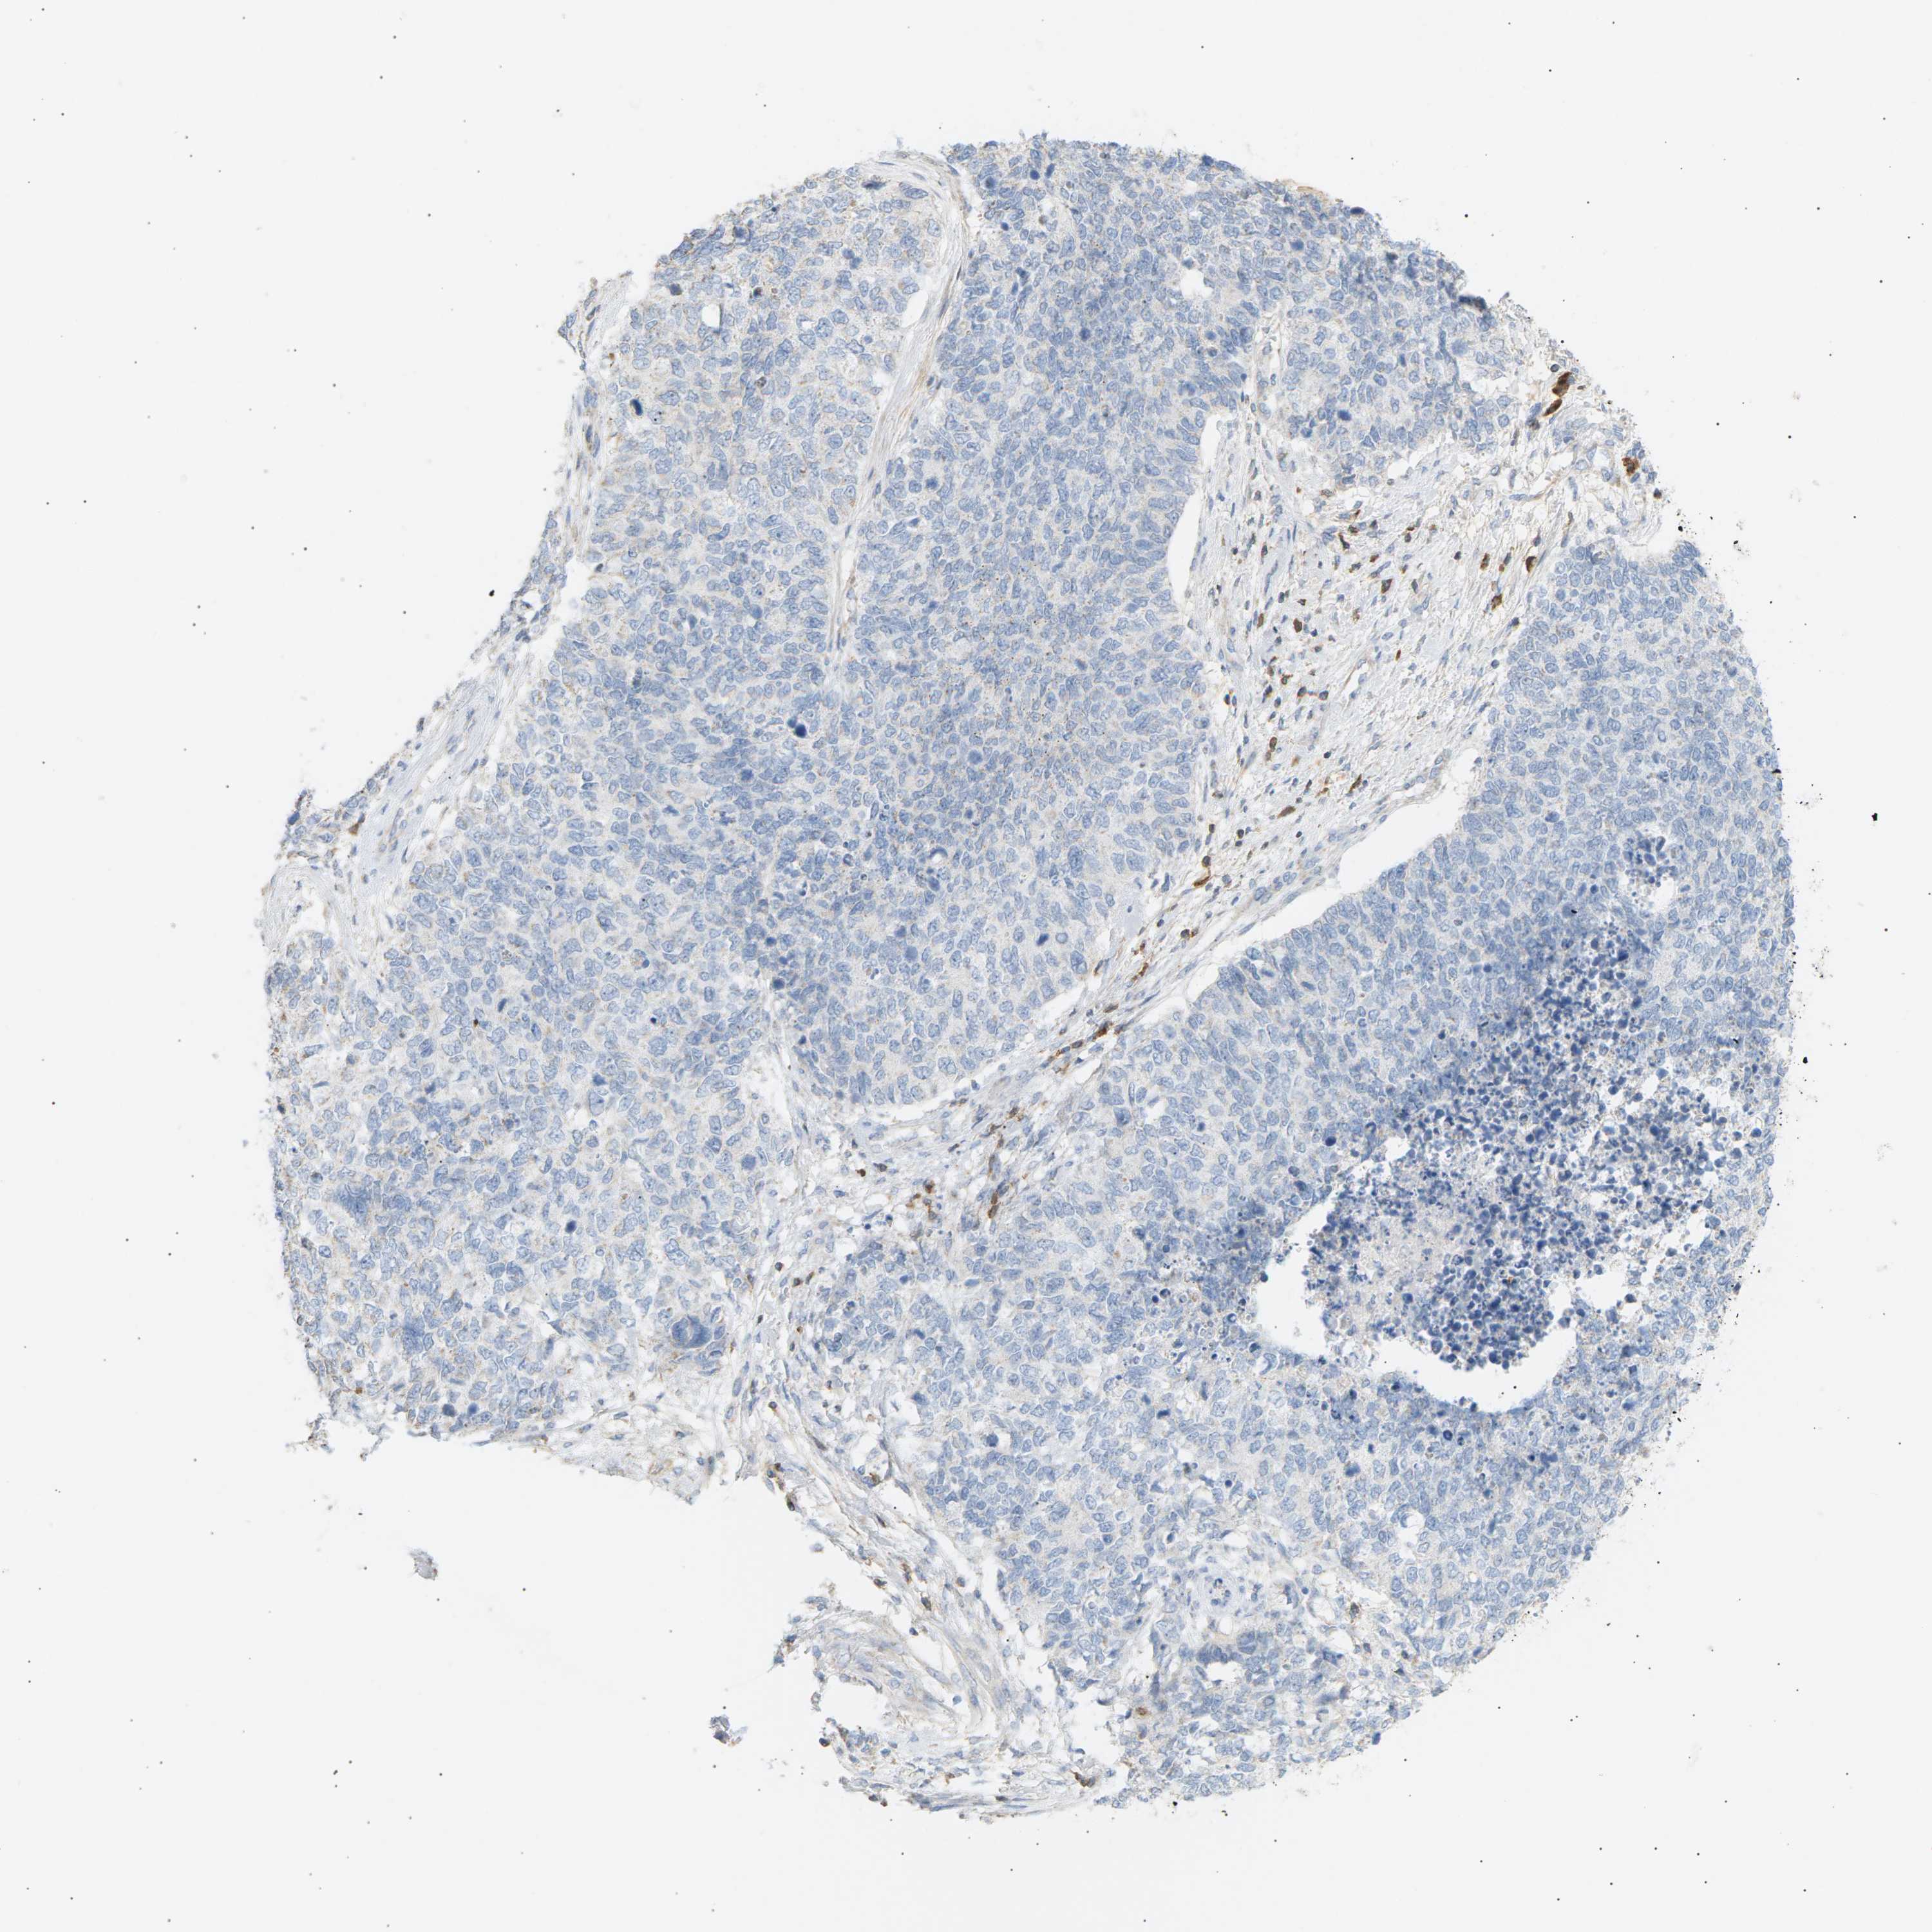

CERVICAL CANCER - Protein expressioni

A mouse-over function shows sample information and annotation data. Click on an image to view it in a full screen mode. Samples can be filtered based on level of antibody staining by selecting one or several of the following categories: high, medium, low and not detected. The assay and annotation is described here.

Note that samples used for immunohistochemistry by the Human Protein Atlas do not correspond to samples in the TCGA dataset.

Antibody stainingi

Antibody staining in the annotated cell types in the current human tissue is reported as not detected, low, medium, or high, based on conventional immunohistochemistry profiling in selected tissues. This score is based on the combination of the staining intensity and fraction of stained cells.

Each image is clickable and will lead to virtual microscopy that enables deeper exploration of all samples and also displays staining intensity scores, fraction scores and subcellular localization as well as patient and tissue information for each sample.

Antibody CAB015363

Staining

High

Medium

Low

Not detected

Intensity

Strong

Moderate

Weak

Negative

Quantity

>75%

75%-25%

<25%

None

Location

Nuclear

Cytoplasmic/membranous

Cytoplasmic/membranous,nuclear

Adenocarcinoma, NOS